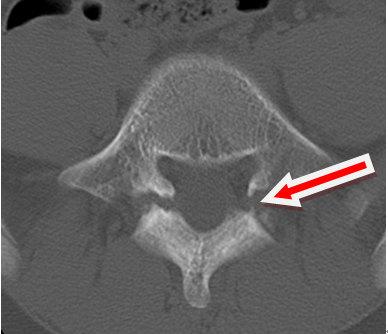

影像学(CT)检查资料:

影像学资料解读:影像学检查可见L5/S1双侧椎弓峡部裂并椎体I°滑脱,椎间盘无退变。

确诊:腰椎峡部裂